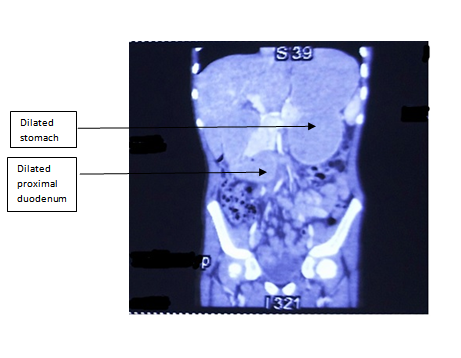

A 10 year old male chid presented with epigastric pain which relieves on vomiting for 10 days. There was a history of significant weight loss of the child secondary to fever of unknown origin over a month. On examination, pallor and visible gastric peristalsis were noted. Ultra sonography of the abdomen was normal. Contrast enhanced computed tomography (CECT) abdomen (Figure 1) (Figure 2) was suggestive of SMA syndrome with dilated proximal half of third part of duodenum and narrow aortomesenteric angle (<110) along with smaller aortomesenteric distance (<5mm). A conservative trial was attempted with nasogastric decompression, IV fluids, total parenteral nutrition and lying on left side or prone position, but proved to be ineffective as the symptoms persisted. Hence, exploratory laparotomy was planned after one week which confirmed the obstruction at the level of third part of duodenum with grossly dilated stomach and proximal duodenum above the level of origin of SMA from aorta and collapsed distal bowel (Figure 3). A side to side retrocolic duodenojejunostomy bypass was done. Postoperative period was uneventful. Oral feeds were started on 6th postoperative day and the patient was discharged on full feeds on 8th postoperative day. The child is asymptomatic and has gained weight on one year follow up.

Figure 2 CECT Abdomen (coronal view) showing dilated stomach and proximal duodenum (marked with black arrows) along with collapsed distal small bowel at the origin of SMA.